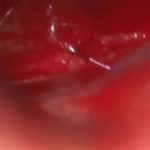

術中写真

摘出 中